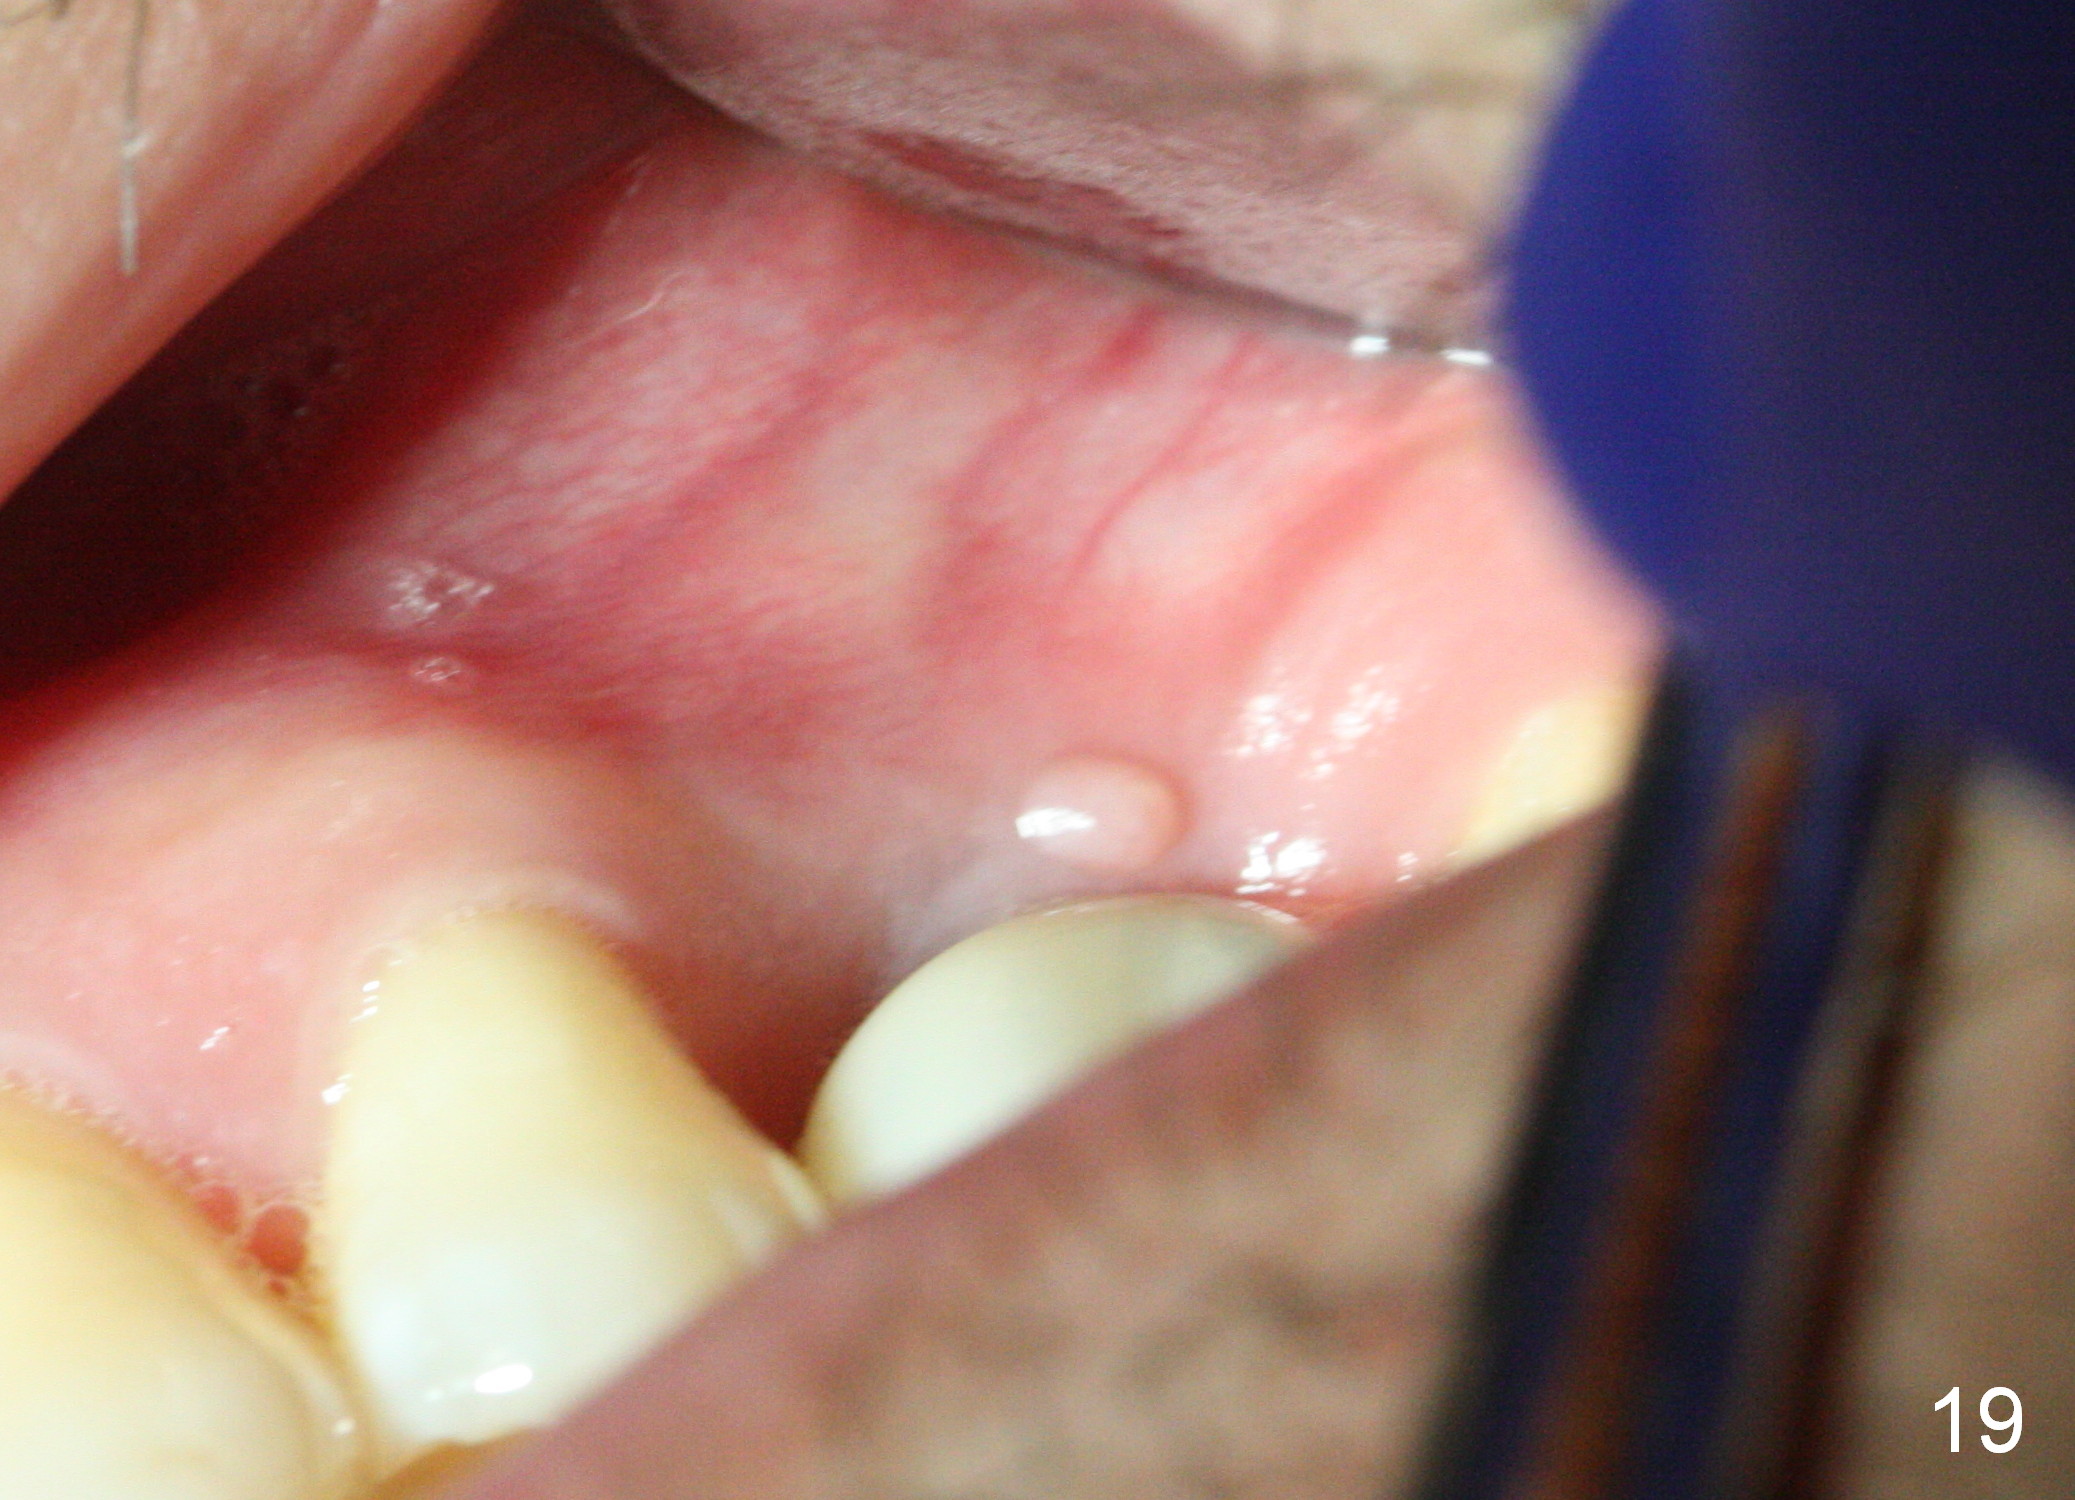

A 45-year-old man has lost the tooth #14 for a while (Fig.1); bone height is 5.4 mm. An extra wide and short implant is planned. Torus palatinus is large, suggesting that bone density should be high. A 6 mm tissue punch is chosen, but it is placed more palatal. If it were placed in the middle of the ridge, there would be no buccal keratinized gingiva (incision may avoid this issue). Additionally, the buccal portion of punch is made incomplete so that there is pedicle on the buccal side when the flap is raised (Fig.4,8: F). It is expected that the excess portion of keratinized tissue will form thick gingiva buccally. Osteotomy proves that bone is dense (Fig.2 (4.5x11 mm tap). Typical sinus lift is finished with placement of 6.4x6 mm (extra wide) bone-level implant (Fig.3, >55 Ncm). Following further torque, Fig.4 shows that the implant (I) is sub-gingival (<). Bitewings are taken to confirm that the implant plateau is at the crestal level (Fig.5,6 ^). PA shows sinus lift (Fig.7 *). The lingual aspect of the implant and healing abutment (H) is further bone grafted and covered by collagen dressing (Fig.8 *). The wound is protected with perio dressing. When the latter dislodges 7 days postop, the collagen dressing and bone graft are lost as well (Fig.10), while the buccal flap remains vital (Fig.9). The lingual exposed plateau should be able to heal normal. The collagen dressing should have been fixed in place by suture or as simple as a dental floss. There is mild nasal hemorrhage 1-2 days postop, possibly related to sinus membrane perforation and inability of Collagen Dressing to cover the perforation and contain the bone graft. When the patient returns for #9 implant placement in 3 weeks postop, the buccal flap reduces in size (Fig.11 *), while the palatal wound has healed with minimal exposure of the implant (Fig.12). Sinus graft remains in place 3 months postop (Fig.13); the buccal flap appears to have incorporated into a part of the gingiva (Fig.14). The bone density of the sinus lift appears to increase 10 days later when an abutment is placed (Fig.15 *). Although oral hygiene is pristine, there is apparent crestal bone resorption 12 months (Fig.16) and 20 months (Fig.17) post cementation, probably due to unfavorable crown/implant ratio and bruxism as well as pre-implantation bone loss (Fig.18,19). In contrast, an immediate implant in the same patient avoids pre- or post-implantation bone loss. In fact both the soft (Fig.20) and hard (Fig.21) tissues remain healthy 2 years 8 months post cementation. The sinus lift remains 3 years 8 months post cementation (Fig.22), while the crestal bone loss persists. The patients keeps complains of food impaction distal associated with bad smell 4 years 1 month post cementation. In fact the distal proximal contact is within normal limit. The bad smell is probably due to crestal bone loss (Fig.23 (pan), 24 (CT) *) and periimplantitis. Bone graft, PRF and Cytoplast membrane will be needed and fixed in place with long healing screw. When the patient returns for crown redo, he also reveals floss related gingival hemorrhage. There is pain associated with palatal sulcus probing with light gingiva erythema. Review of CT coronal section shows possible palatal (Fig.25 P) bone loss (*).